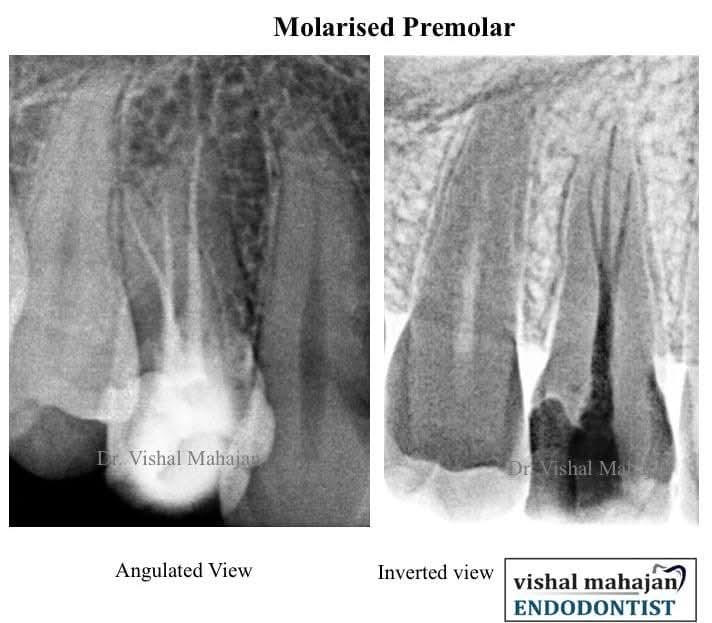

Root Canal Treatment

A Single Visit Root Canal Treatment (RCT) is a modern dental procedure where the entire root canal process is completed in just one appointment.

Dental Microscope

A Dental Microscope is an advanced tool used in modern dentistry to provide high magnification and better visibility, especially during precise treatments like Root Canal Therapy.

- We use the latest dental technology including digital X-rays, intraoral scanners, loupes, and laser treatments.